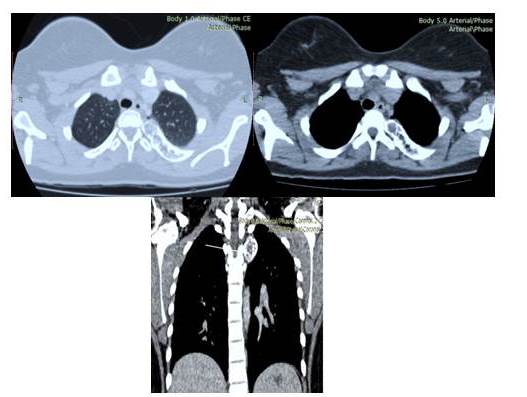

En la tomografía computada de tórax con reconstrucción en 3D, se evidenció imagen hiperdensa con áreas hipodensas en su interior, redondeada de bordes bien definidos microlobulados que mide 4,3 cm x 4,3 cm, a nivel del 1/3 proximal del tercer (3er) arco costal posterior izquierdo con protrusión de dicha lesión hacia parénquima pulmonar y partes blandas dorsal compatible con lesión neoplásica benigna. Resto del plano óseo y blando sin evidencia de lesiones (Figura 2).